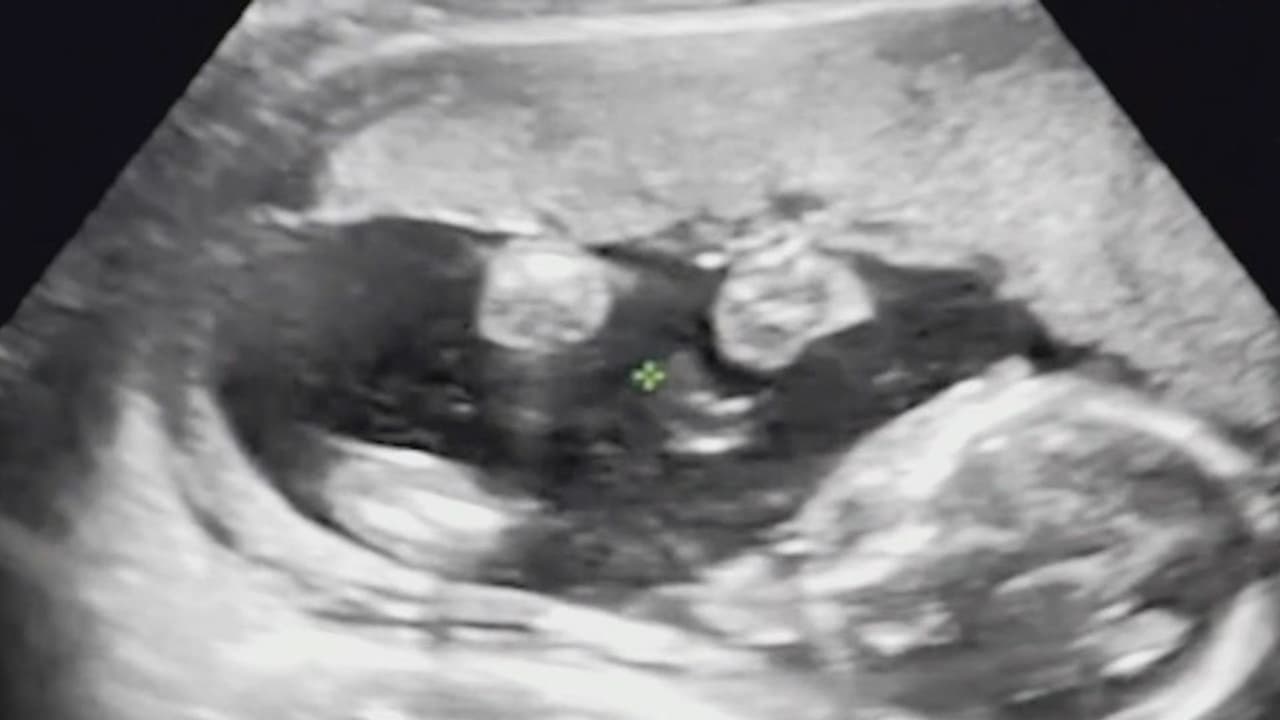

Ken Paxton, fiscal general de Texas, presentó una demanda en contra de la Dra. Margaret Carpenter, de Nueva York, por recetar unos medicamentos abortivos a una joven de 20 años por medio de telemedicina. Paxton argumenta que la mujer reside en Texas y proporcionar este tipo de fármacos es ilegal.